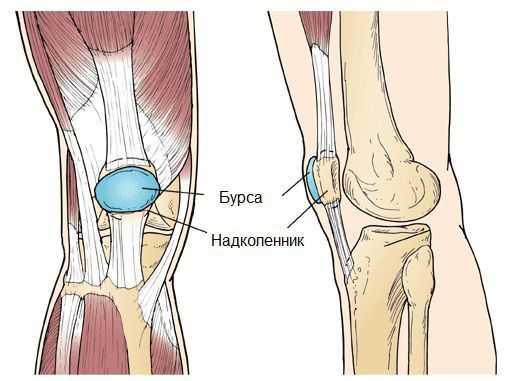

Синовиальная сумка (или бурса) — это небольшая полость с жидкостью. Бурсы расположены в местах наибольшего трения различных тканей: сухожилий, мышц и костных выступов. Благодаря нормальному функционированию суставных сумок, трение при движении уменьшается. Стенка бурс двухслойная: наружный слой состоит из плотной соединительной ткани; внутренний называется синовиальной оболочкой, в норме он вырабатывает небольшое количество жидкости. При нарушении работы синовиальных сумок движения сустава невозможны.

Коленный сустав — один из наиболее сложных суставов в теле человека. Он имеет в своём составе большое количество синовиальных сумок:

- наднадколенниковая (супрапателлярная);

- преднадколенниковая (препателлярная);

- поднадколенниковые поверхностная и глубокая (инфрапателярные);

- сумка гусиной лапки (анзериновая);

- сумка медиальной (внутренней) боковой связки;

- сумка латеральной (наружной) боковой связки;

- сумка илиотибиального тракта;

- сумка сухожилия полуперепончатой мышцы (полуперепончатая);

- сумка медиальной (внутренней) головки икроножной мышцы — икроножная сумка;

- сумка подколенной мышцы — подколенная.

Бурсит может возникнуть в любой из этих видов сумок [10] .